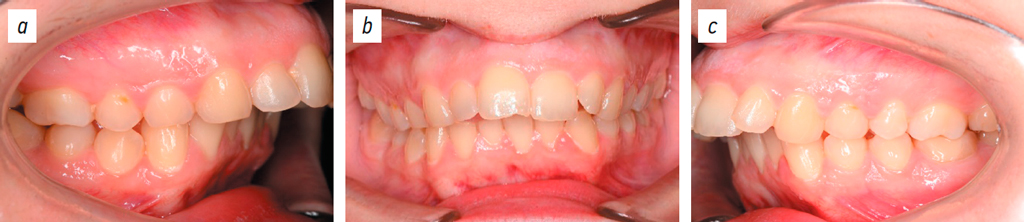

The outcomes of orthodontic treatment are presented in Figs. 19–21.

Fig. 19. Dental arches: lateral right projection (a), posteroanterior projection (b), lateral left projection (c).

Рис. 19. Зубные ряды: боковая правая проекция (a), передняя проекция (b), боковая левая проекция (c).

This clinical case demonstrated a 2-fold reduction in treatment duration compared to conventional approaches.